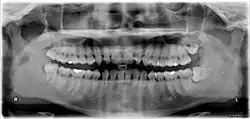

Die folgenden Röntgenbilder sind Ausschnitte aus Orthopantomogrammen (OPG):

Weisheitszahn 38; retiniert und verlagert; mesiale Kippung um fast 90°

Weisheitszahn 38; fast bis zur Kauebene durchgebrochen; distale Wand vollständig im Knochen; voll ausgebildete Wurzel; Wurzelspitzen projizieren sich auf den Nervus alveolaris inferior

Weisheitszahn 38; retiniert und verlagert – stark nach mesial gekippt; sehr kurze Wurzelspitzen projizieren sich auf den Nervus alveolaris inferior

Weisheitszähne 48 und 18; Zahn 48 – keine Kippung, Wurzel nur teilweise ausgebildet, Krone teilweise noch knöchern bedeckt

Weisheitszahn 38 angelegt; retiniert – Krone unter Zahn 37 verkeilt; Krone okklusal nicht mehr von Knochen bedeckt; nur eine Wurzel sichtbar – relativ kurz aber voll ausgebildet.

Weisheitszahn 38 angelegt – fast noch keine Wurzel ausgebildet; mesial gekippt.